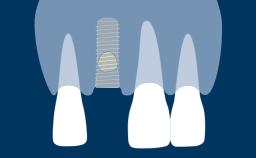

The single tooth replacement with an implant-supported crown is a frequent indication for implant therapy.

In the anterior maxilla, not only does the prosthetic replacement need to re-establish function, it also needs to satisfy esthetic expectations.

To achieve optimal esthetic outcomes, the implant prosthesis must mimic the adjacent natural teeth in color and shape.

In addition, the peri-implant soft tissues on the facial aspect must appear similar to the gingivae of the adjacent teeth in volume, contour, color, and texture.